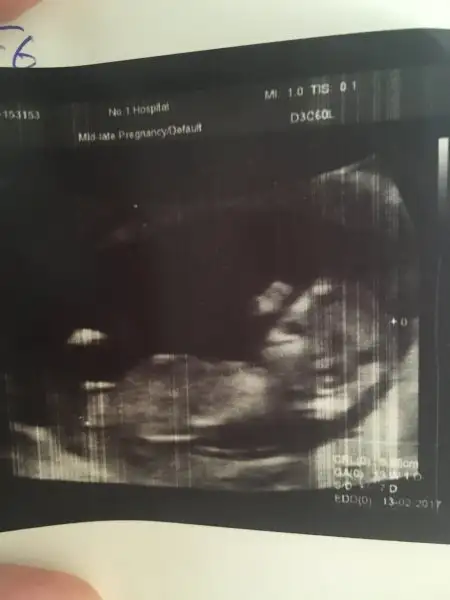

Slm kızlar hastaneden geliyorum. Kıpır kıpırdı sürekli el salladı minnak. Ense kalınlığı 1,3 çok iyi dedi doktor. 12 haftalık bugün tam ama 13+1 çıktı. Boyu 7cm olmuş. Fotosunu yükleyeyim bakalım cinsiyet için, doktor göstermiyor dedi sadece

Eklentiler

• image.webp

8,4 KB · Görüntüleme: 71

maşallah annesi yaaa.. sanki ağzı açık gülüyor gibi